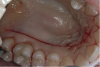

To procure a FGG, the tissue to be harvested is outlined using a #15C scalpel, then any rugae on the graft are smoothed off with a coarse #10 round diamond bur before removal of the graft (Figure 1). Smoothing the rugae reduces its appearance on the graft postoperatively for esthetic purposes and ensures equal thickness of the graft while it is being removed from the palate. Typically, a FGG is 1.5 mm to 2 mm thick. However, if more thickness is needed to try to gain root coverage, 2 mm to 2.5 mm can be harvested.18

Fig 1. To begin harvesting a FGG, a rectangle of tissue is outlined using a #15C scalpel; rugae are smoothed from the graft prior to removing it.